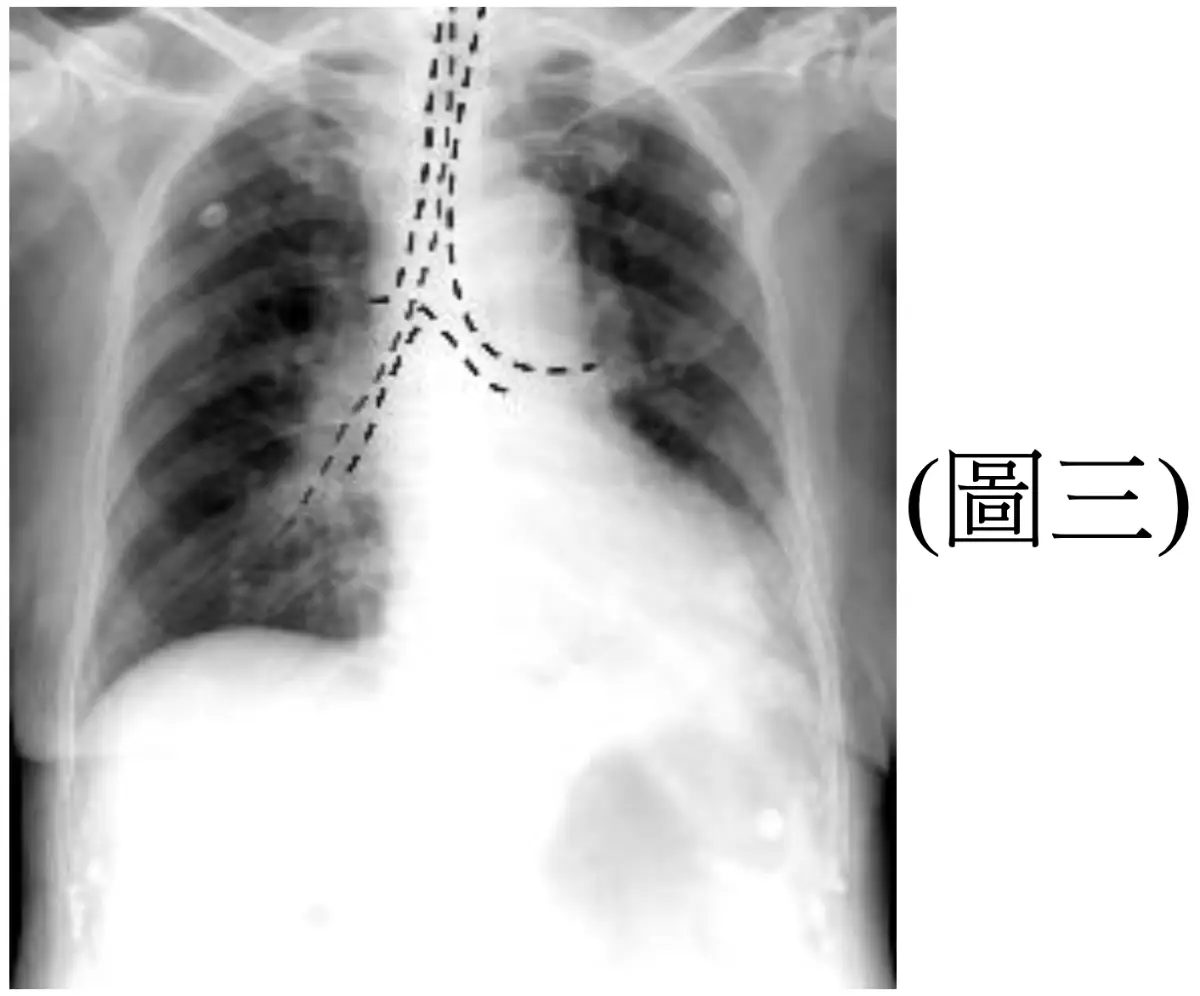

一位 82 歲女性,二天前灌食時發生嗆咳,今日因發燒、喘咳,被家屬送來醫院治療,病人神智不清,血壓90/50 mmHg,心跳130次/分,呼吸喘促,聽診肺部多痰音,來院後所照胸部X光如(圖二)、氣管及鼻胃管位置解析如(圖三),此時不宜進行何項處置?

• 兩天前灌食時嗆咳,今日發燒、咳喘,胸部 X 光呈右下肺大片浸潤,符合吸入性肺炎。

• 另張影像可清楚看到鼻胃管沿氣管向下,而非經食道進入胃內 → NG tube 錯置於呼吸道。此錯置正是吸入性肺炎的誘因。